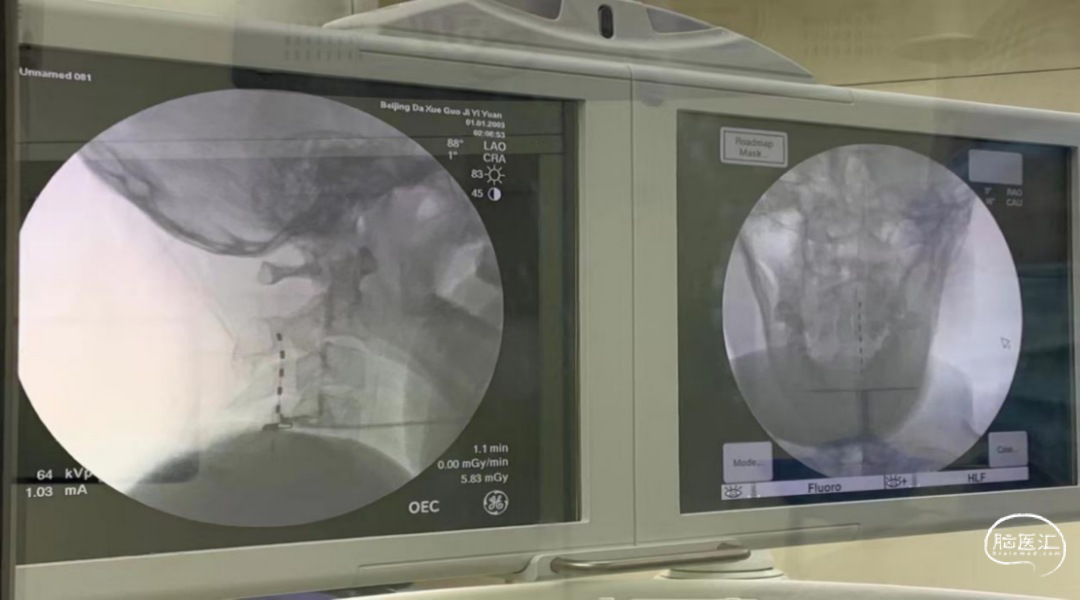

经过一系列的检查和治理,判定患者唤醒的希望很大。团队于2021年8月6日行经皮穿刺脊髓电刺激术,对患者进行为期14天的短时程刺激治疗。

患者术中的影像